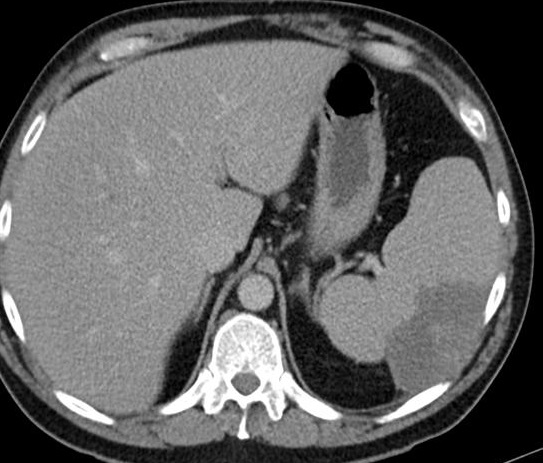

Image radiologique TDM

de hematome intra-parenchymateux de la rate est

aspect arrondie ou ovalaire hypodensite a contours

nette , moin regulier . Image radiologique d'une

traumatisme /contusion de la rate en coupe axiale |

Image radiologique TDM en

coupe axiale d'une traumatisme de la rate avec

aspect lesionnel de hematome intra-parenchymateuse

hypodense en forme ronde , lobulaire a bord nette et

irreguliers |